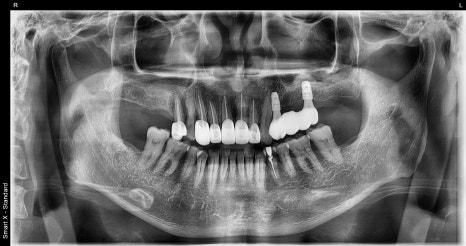

🖼️ 치료 전 후 비교 사진

치료 전후 파노라마 X-ray 비교 사진 (왼쪽: 초진 / 오른쪽: 치료 후)

환자분도 치료 내내 꾸준히 내원해주셨고,

저희도 각 단계마다 최선을 다해 도와드린 덕분에

사고 이전보다 더 건강한 구강 상태로 회복된 사례였습니다.